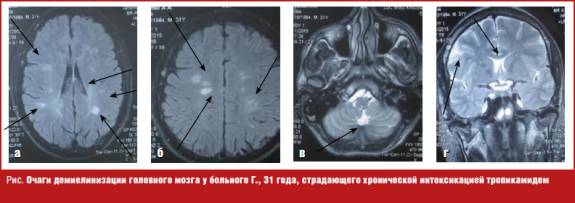

С целью дообследования больному проведена магнитно-резонансная томография (МРТ) головного мозга, на которой выявлены множественные очаги демиелинизации в белом веществе лобных, теменных, височных и левой затылочной долей, субкортикально и паравентрикулярно, в мозолистом теле, ножках мозжечка, в области базальных структур справа размером от 0,3 до 1,0 см без четких контуров, некоторые из них с явлениями перифокального отека (рис. (а, б, в)).

В литературе описаны случаи диффузного повреждения белого вещества у пациентов с дезоморфиновой наркоманией, приводящей к тяжелым расстройствам когнитивных функций, астазией-абазией, экстрапирамидным нарушениям. В данном случае множественное повреждение структур головного мозга в виде рассеянных очагов демиелинизации белого вещества лобных, теменных, височных и затылочной долей, расположенных субкортикально и паравентрикулярно, очагов демиелинизации в мозолистом теле, ножках мозжечка, в области базальных структур, протекающих без какой-либо очаговой пирамидной и экстрипирамидной симптоматики и чувствительных нарушений, возможно, обусловлены систематическим токсическим действием тропикамида, хотя в литературе описаны случаи очаговой демиелинизации вследствие сосудистых, опухолевых и инфекционных поражений [8]. В связи с вышеизложенным для окончательного установления причины морфологических изменений головного мозга в данном случае целесообразно проведение прижизненной биопсии головного мозга, от которой пациент отказался. Магнитно-резонансная томография с контрастным усилением, рекомендованная пациенту через 6 месяцев, проведена не была в связи с развитием у пациента в указанные сроки острого психоза и госпитализацией его в психиатрическое отделение.